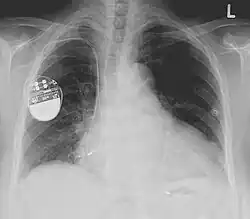

Pacemaker

Een pacemaker is een apparaat dat ervoor zorgt dat het hart in het juiste ritme blijft pompen door elektrische impulsen te genereren geleverd door elektrodes. Aanvankelijk werden pacemakers gebruikt om een te traag hartritme (bradycardie) te corrigeren. Later werden ze ook toegepast bij een te snel hartritme (tachycardie), en bij patiënten met een risico op een hartstilstand of met hartfalen. Het apparaat ter voorkoming van een hartstilstand wordt implanteerbare cardioverter-defibrillator (ICD) genoemd. Bij hartfalen wordt een biventriculaire pacemaker ingezet. Als het hart stil komt te staan of onregelmatig klopt, zal de pacemaker een elektrische prikkel geven, waardoor de normale hartslag hersteld wordt.

Pacemakers worden gevoed door 2,5 volt lithium-iodine batterijen. Een pacemaker gaat zo'n acht tot tien jaar mee, daarna moet hij worden vervangen. De apparaatjes zijn klein; ongeveer 20 cc en 20 gram zwaar. Ze kosten gemiddeld zo'n 3000 euro. Doordat ze meestal vlak onder de huid geïmplanteerd worden, is dit geen ingrijpende zaak. Men verblijft meestal één nacht na de ingreep in het ziekenhuis ter observatie. Het vervangen van de pacemaker kan in dagopname; het is een kleine ingreep.